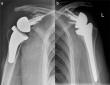

Shoulder Arthroplasty Market Projected To Reach $1,814 Million By 2028 - Medical Product Outsourcing

Asia-Pacific witnessed highest growth rate for shoulder arthroplasty market and is expected to continue this trend throughout the forecast period. NE WIN SIVERS DRIVE, PROVINCE: - PORTLAND, UNITED STATES, December 6, 2021 /EINPresswire.com/ -- According …